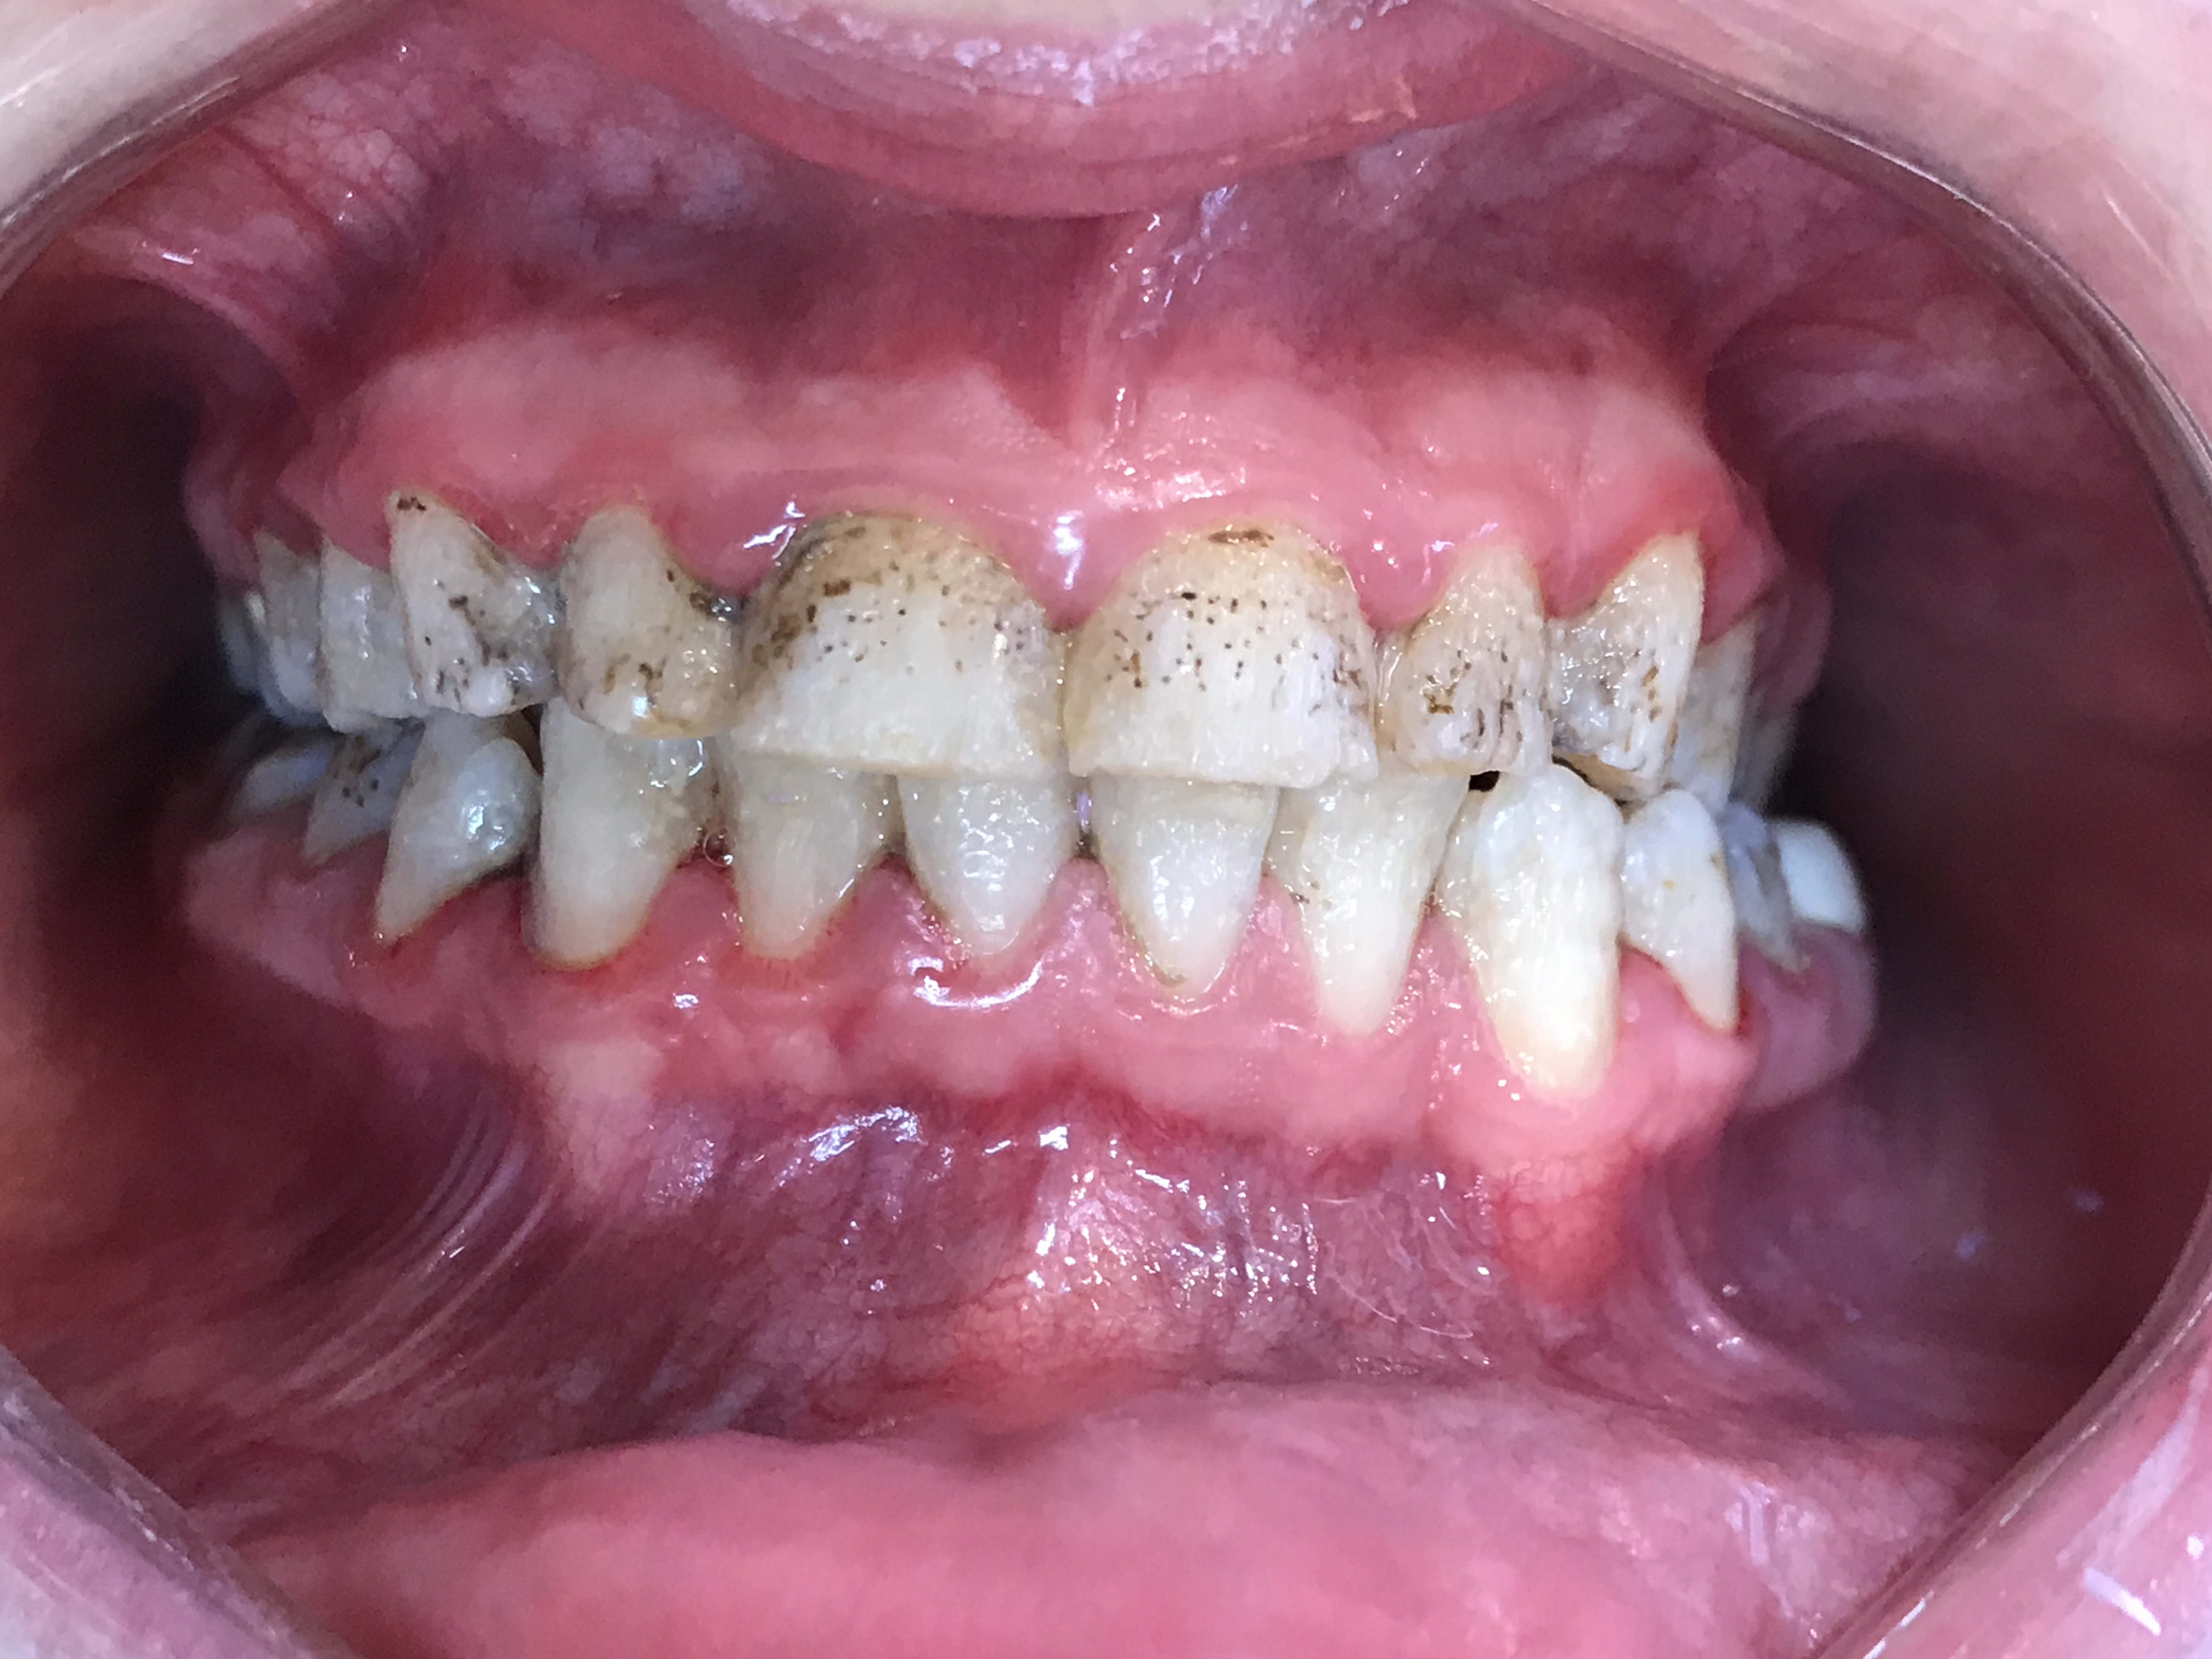

Patiente avec amelogenese imparfaite dont je prévois peut etre de faire des facettes de 13 à 23.

La qualité de l'émail est elle la meme une fois fraisée ? L'adhésion est elle bonne ? Des précautions particuliere a prendre dans ce type de cas ?

Attention à l'adhésion sur ce type d'émail.

t'as vu le niveau d'inflammation de la gencive ??? un coup de soufflette entre deux dents et ça pisse le sang...

Regardes comment est l’émail juxta ou sous gingival , si c'est tout grêlé je me poserai même pas la question ---> CCM

après préparation et juste avant le collage, il faudra préparer l'émail 1 minute avec de l'hypochlorite, puis 3 minutes à l'acide orthophosphorique à 37%.

Les faces proximales sont moisies ,

Les faces occlusales ne sont pas fonctionnelles .

Il y a une occlusion inverse derriere